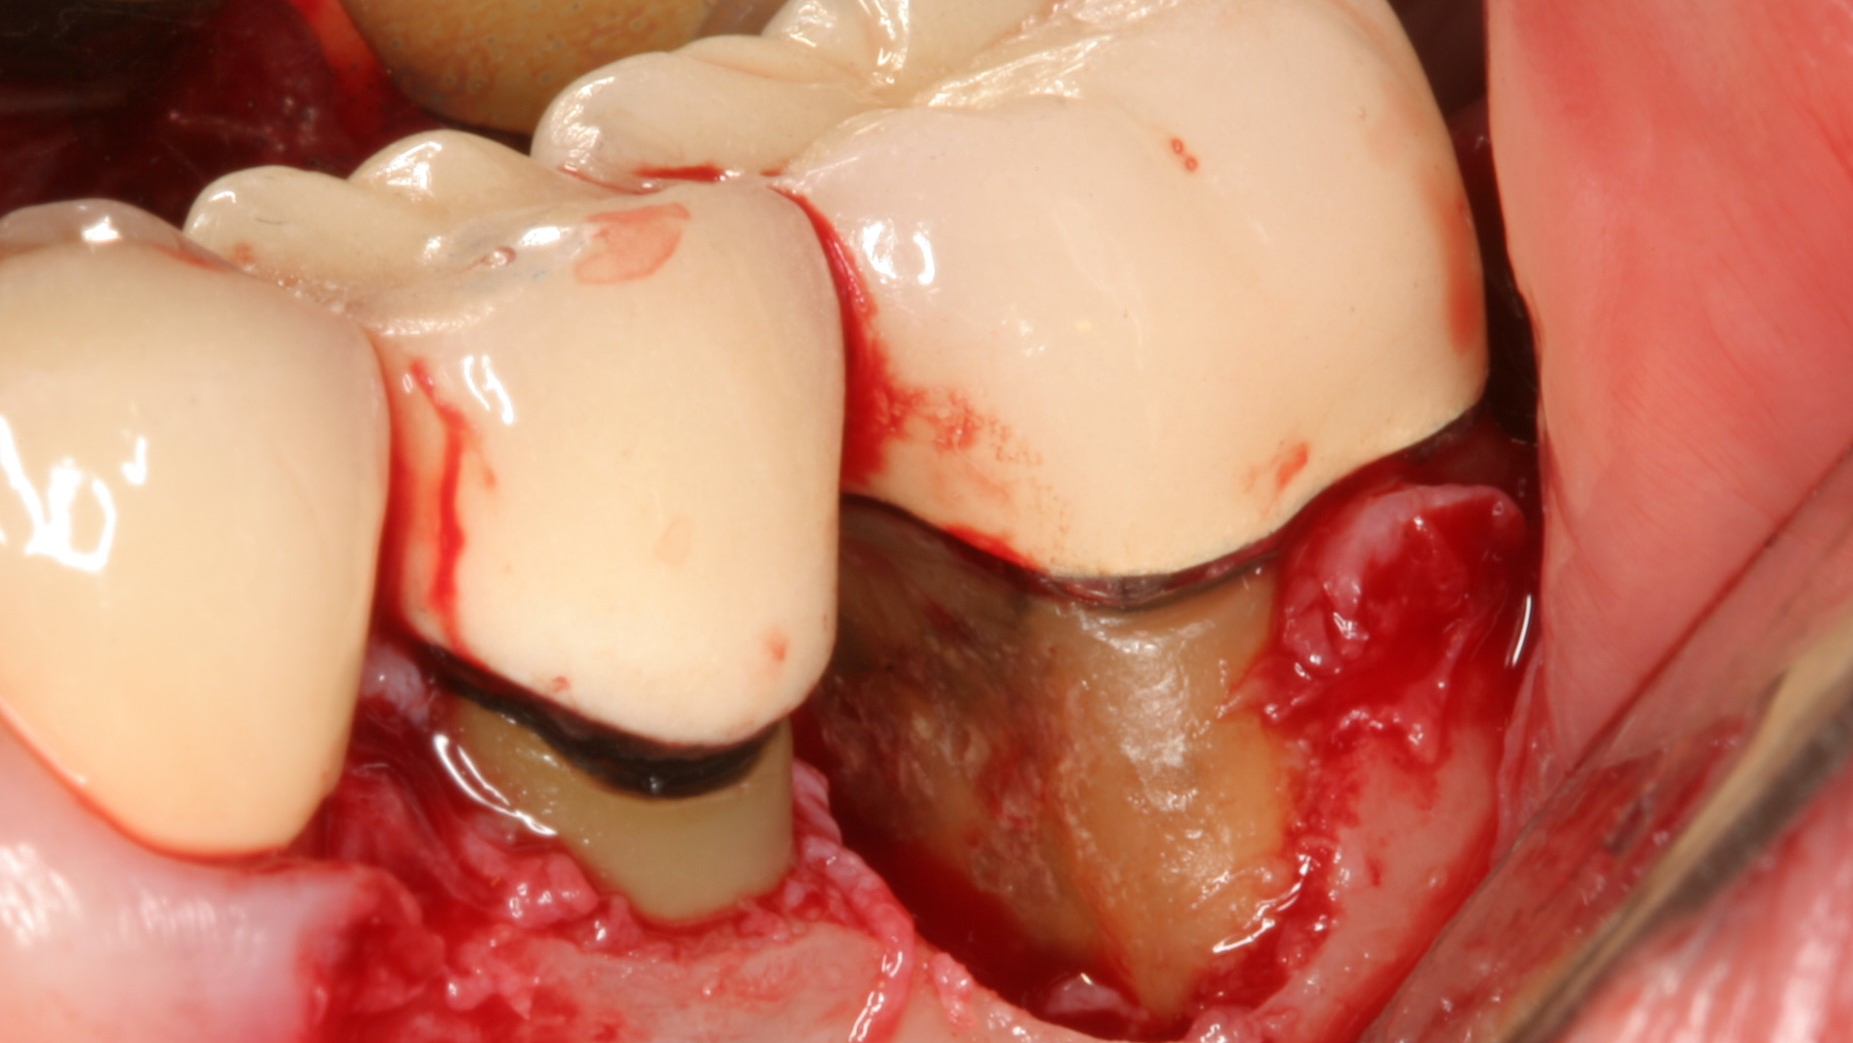

In this gallery, you’ll learn how to decontaminate and graft a case of moderate peri-implantitis, use AI to predict those at risk for peri-implant disease, and more.